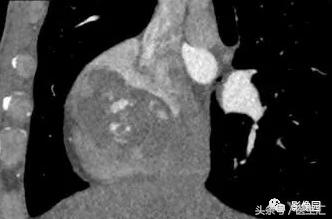

①发病部位:93%的原发性心脏血管肉瘤发生在右心房壁;

②强化特征:心脏CT及MRI增强扫描均见肿瘤实质部分明显不均匀延迟强化,心脏CT增强扫描可见粗大肿瘤血管影或血管团,提示该病为富血供肿瘤,可作为该病的另一鉴别点。MRI上很难见到粗大肿瘤血管影或血管团,可能与其空间分辨力较低有关。另有文献报道,该肿瘤组织摄取钆对比剂后呈现“日光放射状”外观。

③生长方式:原发性心脏血管肉瘤沿右心房游离壁浸润蔓延,可向心房腔内或腔外生长。